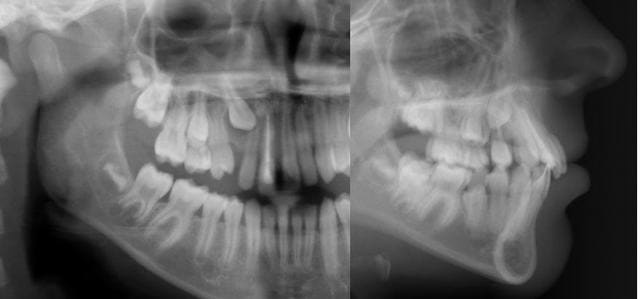

Voici un cas où ta technique, Dancha, va devoir faire des miracles.

Le souci va être le dégagement chirurgical de 23 et 24.

âge 53 ans

Autant je suis optimiste et assuré du résultat lorsqu’il s’agit d’un adolescent, autant j’émettrai des réserves pour un cas d’inclusions multiples à cet âge là. Cependant on ne risquerait pas grand-chose à tenter une traction sur la 25 et au cas où celle-ci viendrait essayer ensuite de dégager les autres. Un ressort baliste sur deux micro-vis a l’avantage d’être relativement aisé à réaliser, d’être discret et très bien toléré. Je pense que cela vaudrait la peine d’essayer si le patient est d’accord.

Cela fait quand même penser à une dysostose cléido-crânienne.

aucun risque de dysostose, ce patient est un grand et fort gaillard antillais de 1,88m et 110kg, avec un visage tout ce qu'il y a de charmant.

pour en revenir aux multiples inclusions, quel accés serait possible pour 23 et 24?.

Quand à l’accès pour chercher 23 et 24, je ne me lancerais pas avec juste une panoramique. J’aime bien les télés qui suffisent dans la très grande majorité des cas. En cas de doute, je fais en plus une tomo (j’ai un appareil Planmeca à trois axes qui en fait). Si toi tu ne peux pas en faire, tu peux quand même réaliser une seconde télé en la décentrant pour placer 23 et 24 orthogonales au faisceau ou bien entendu faire faire un scan, plus coûteux.